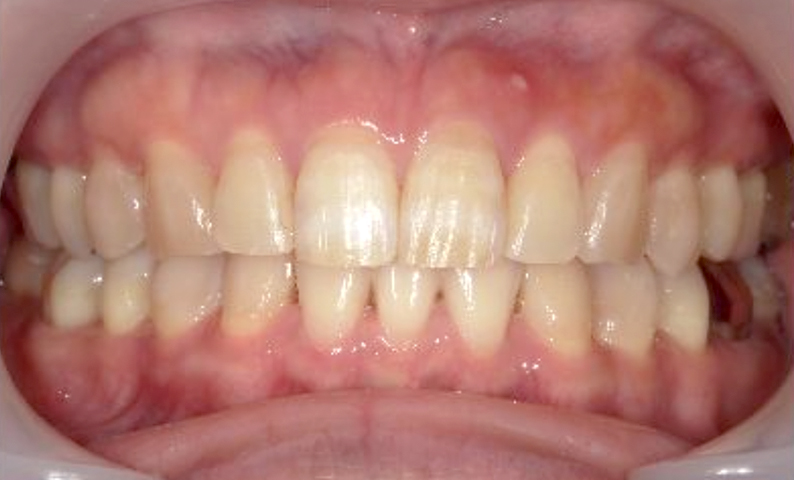

症例_003 下顎だけの部分矯正

治療期間:10ヶ月金額:24万円+税女性前歯のガタガタ下の前歯だけ上顎は補綴治療中

| Before | After |

|---|---|

|